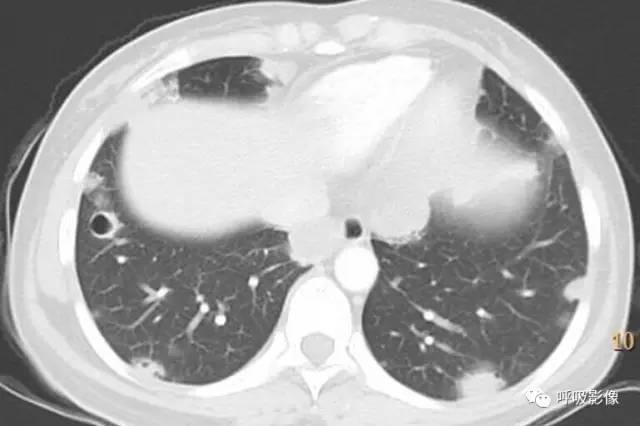

绒毛膜癌较侵袭性葡萄胎易发生转移。侵袭性葡萄胎肺部转移多以结节为主(图1),而绒毛膜癌肺部转移种类较多。

图1 女,31岁,侵袭性葡萄胎